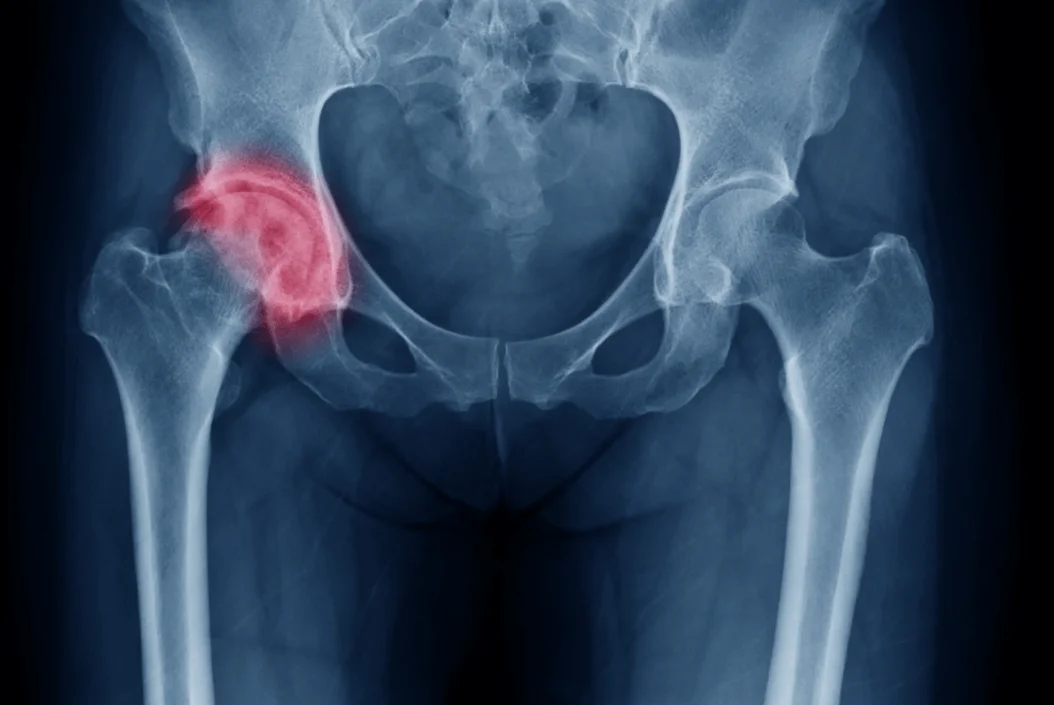

Hip osteoarthritis is a condition where the cartilage in the hip joint wears down over time, causing the bones to rub together. This leads to pain, stiffness, swelling, and trouble walking or moving the hip, especially after sitting or standing for long periods.